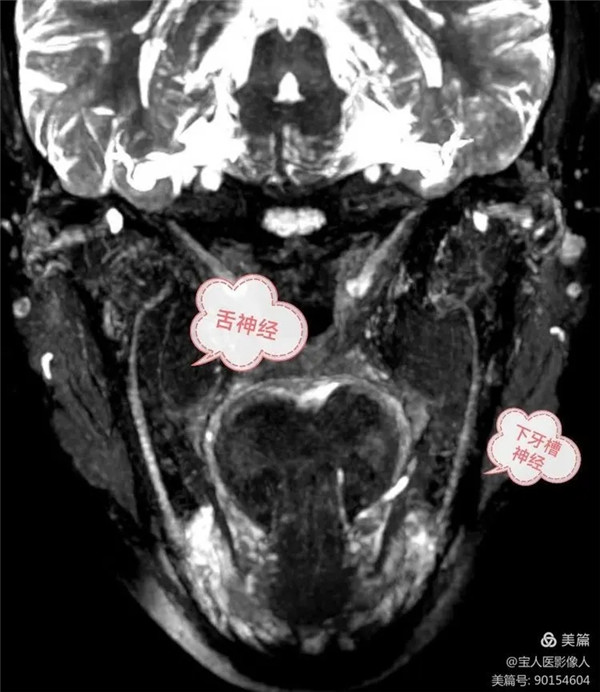

磁共振成像清晰顯示了舌神經和下牙槽神經的走形,粗細及信號

(3) 舌神經在下牙槽神經的前方,經翼外肌深面下行,途中有面神經的鼓索從后方加入此神經。

(4) 下牙槽神經為混合神經,下牙槽神經在舌神經的后方,沿翼內肌的外側面下行,一般軀體感覺纖維經下頜孔入下頜管。在下頜管內分支構成下牙叢,分支分布于下頜各牙和牙齦。